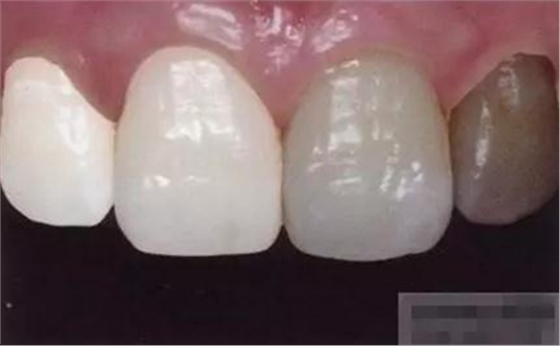

【分層堆塑】

A4本質(zhì)堆塑

Dr.Vanini建議如果牙醫(yī)選色有疑惑的話,最好應(yīng)用顏色深一些的牙本質(zhì)樹(shù)脂。

A3本質(zhì)堆塑

發(fā)育葉制作

白堊斑

切端琥珀色制作

A3頸部堆塑

涂布防氧化劑

充填初步完成

【初步修整】

對(duì)于唇面,首先使用火焰狀車針進(jìn)行修整,一般不使用輪狀車針修整線角

微細(xì)的表面結(jié)構(gòu)最后使用鎢鋼拋光車針成形的。

【充填完成】

1、樹(shù)脂貼面平齊牙齦邊緣是最佳設(shè)計(jì),或者使用齦上邊緣 。

2、釉質(zhì)邊緣要用橡皮輪拋光。拋光可以去除懸釉。這樣經(jīng)過(guò)車針打磨過(guò)的釉質(zhì)表面會(huì)更加均一,形成良好的邊緣封閉。

3、纖維樁通常深入到根管的1/2至2/3處。因?yàn)樽罴训恼辰有Чl(fā)生于根管的冠1/3和中1/3。由于根1/3的牙本質(zhì)小管往往不能充分敞開(kāi),此區(qū)域幾乎沒(méi)有粘接作用發(fā)生,所以,根管纖維樁放置的深度無(wú)需超過(guò)根中1/3。